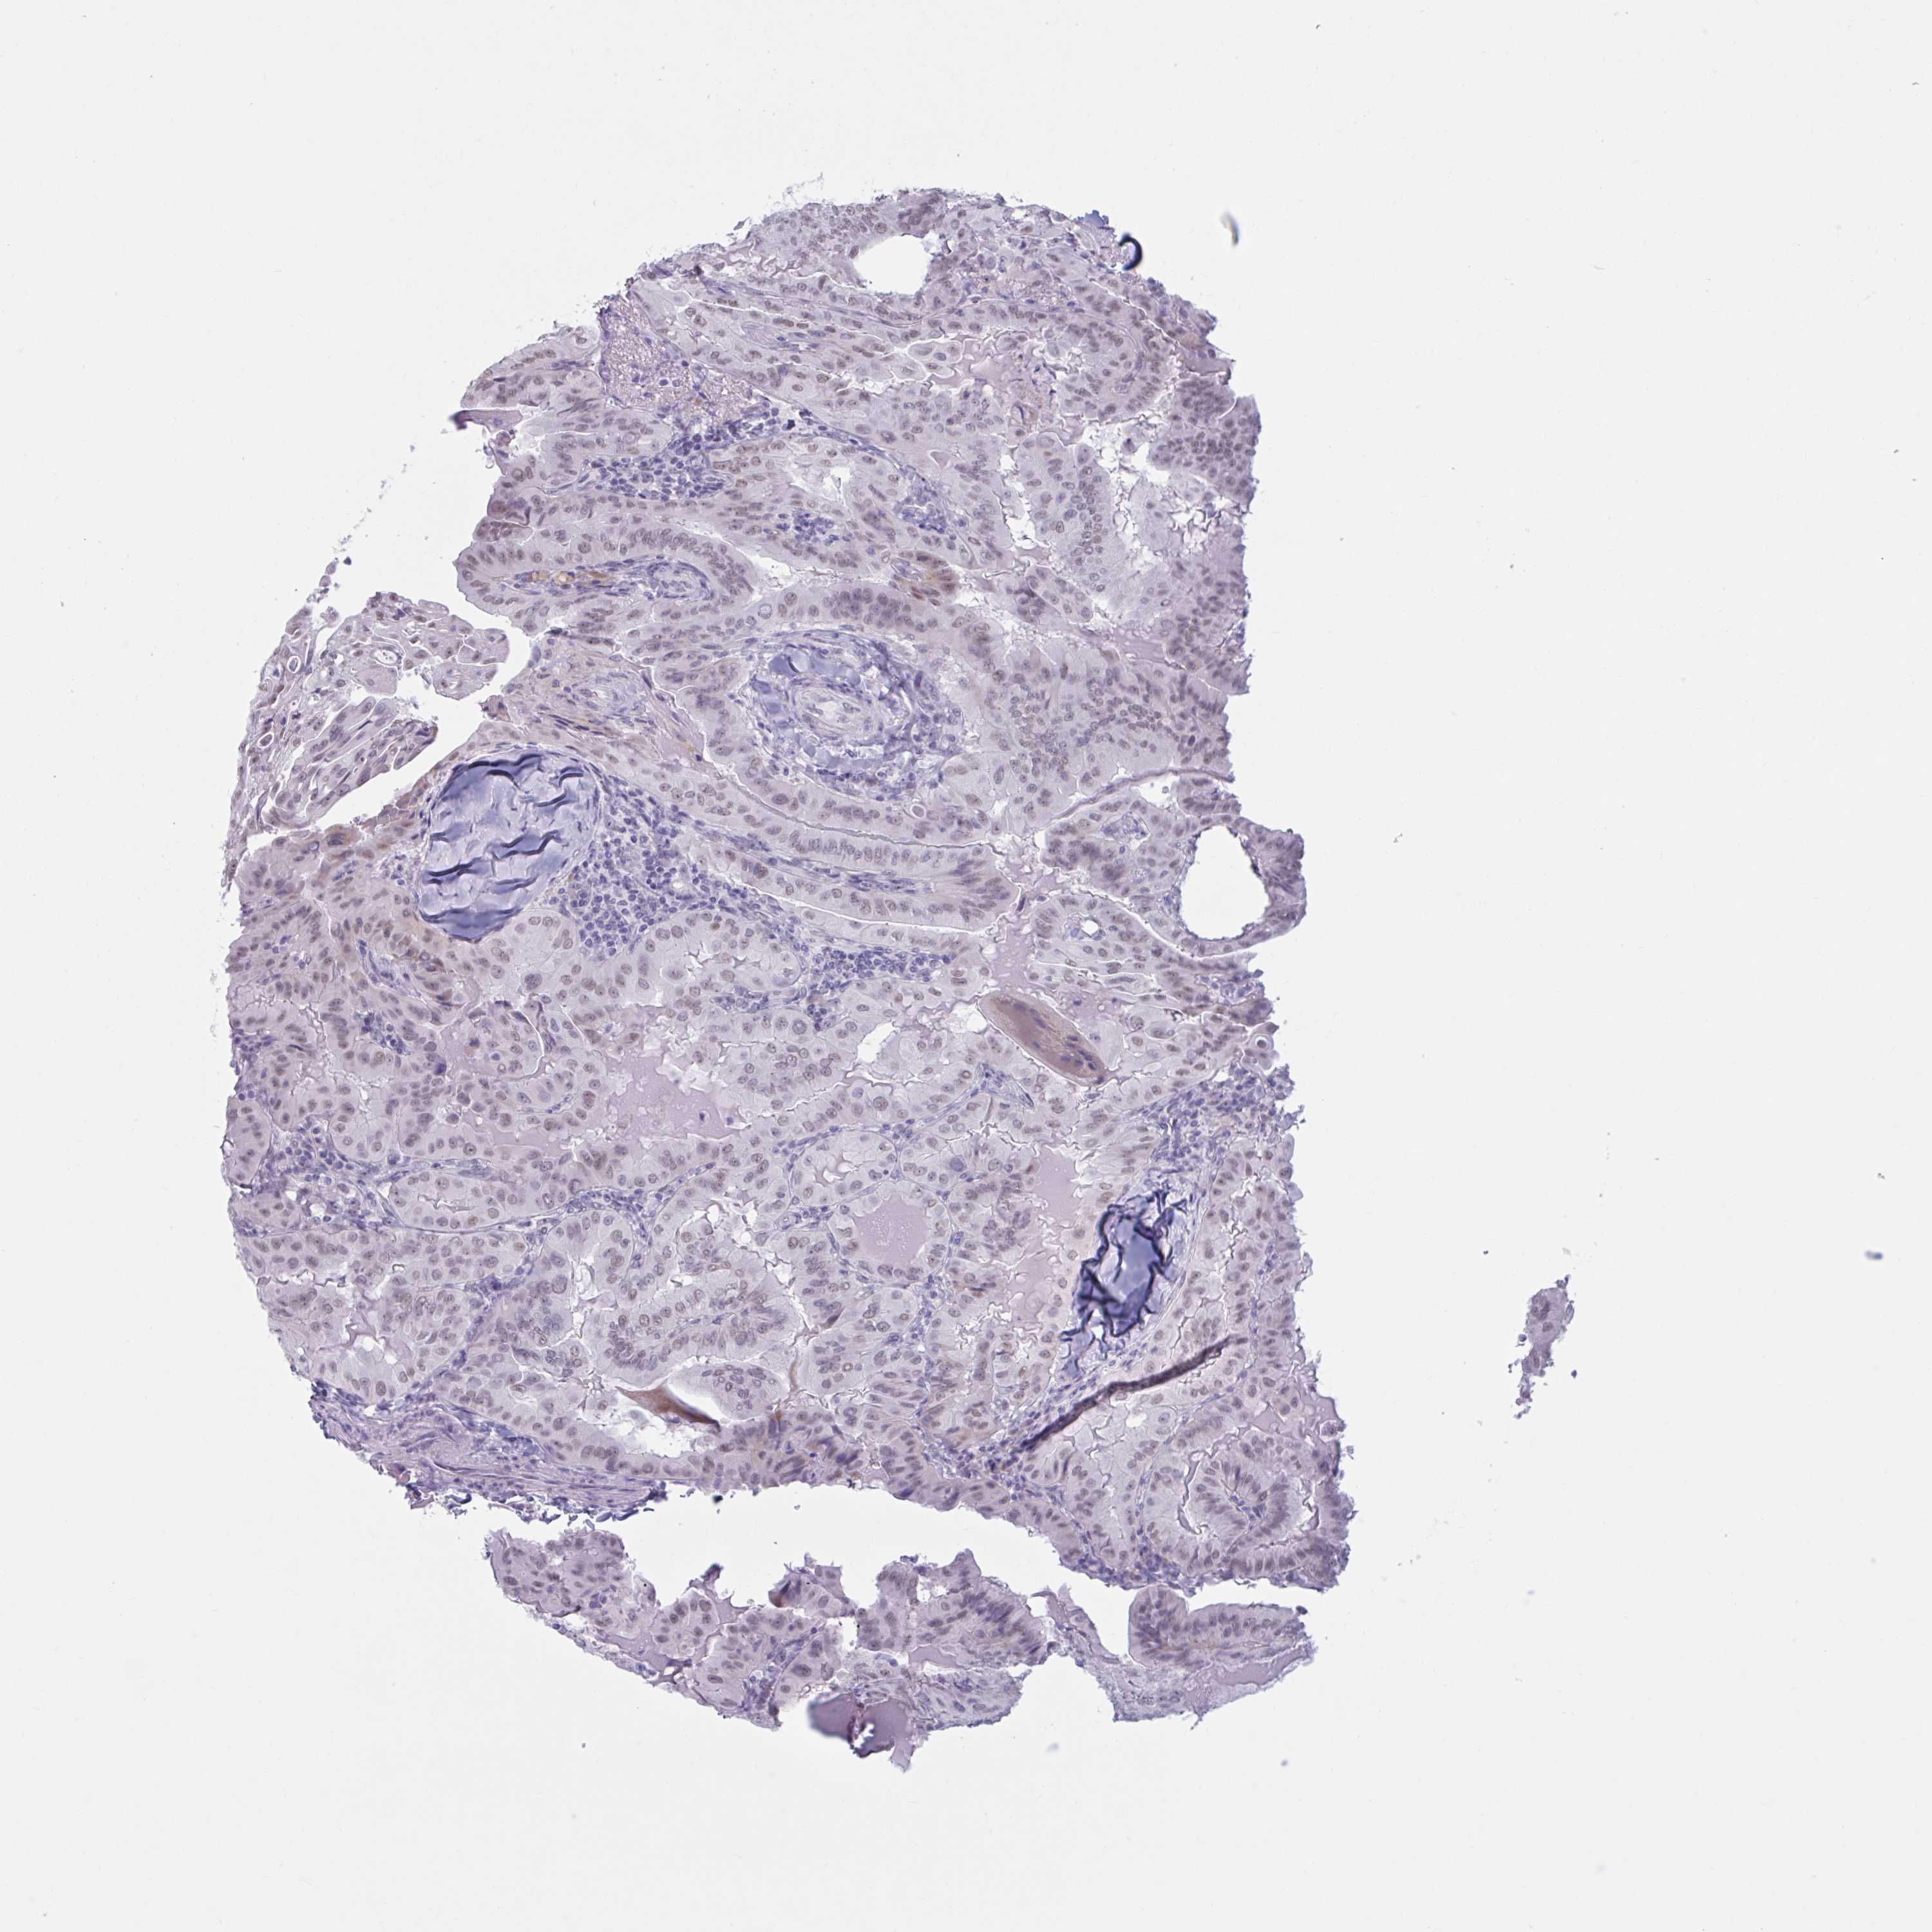

THYROID CANCER - Protein expressioni

A mouse-over function shows sample information and annotation data. Click on an image to view it in a full screen mode. Samples can be filtered based on level of antibody staining by selecting one or several of the following categories: high, medium, low and not detected. The assay and annotation is described here.

Note that samples used for immunohistochemistry by the Human Protein Atlas do not correspond to samples in the TCGA dataset.

Antibody stainingi

Antibody staining in the annotated cell types in the current human tissue is reported as not detected, low, medium, or high, based on conventional immunohistochemistry profiling in selected tissues. This score is based on the combination of the staining intensity and fraction of stained cells.

Each image is clickable and will lead to virtual microscopy that enables deeper exploration of all samples and also displays staining intensity scores, fraction scores and subcellular localization as well as patient and tissue information for each sample.

Antibody HPA051257

Antibody CAB026357

Staining

High

Medium

Low

Not detected

Intensity

Strong

Moderate

Weak

Negative

Quantity

>75%

75%-25%

<25%

None

Location

Nuclear

Cytoplasmic/membranous

Cytoplasmic/membranous,nuclear

Papillary adenocarcinoma, NOS

Follicular adenoma carcinoma, NOS